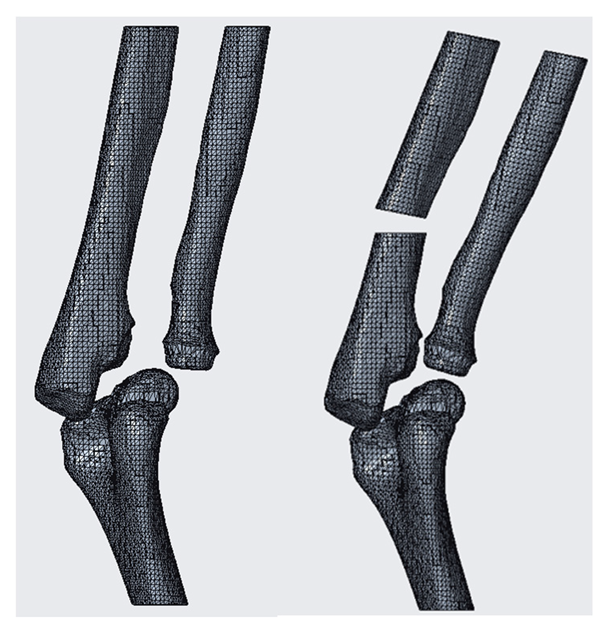

As seen below, to define the references (Figure 7, Figure 8, Figure 9, Figure 10 and Figure 11), complex solids must be approximated to simpler geometries; hence, it will be possible to trace the center planes and points of interest as shown in the figure. Creo allows the selection of each mesh vertex; in this way it can characterize the models in a very precise way and highlight relevant anatomical sections, such as epicondyles or diaphysis axes in long bones.

It is important to remember that the features just described (Figure 12, Figure 13 and Figure 14) are only those functional for the simulation of this pathology. The software makes available many other tools that have been used in the processing of the other cases and that will be illustrated in the results chapter.

The simulation results in a three-dimensional model presenting the anatomical group after the operation (Scheme 1). On it can be detected all the necessary measures in the pre-operative planning phase and the program also allows saving the file in many different types of formats so that it is exportable to other software and not viewable only by CAD.